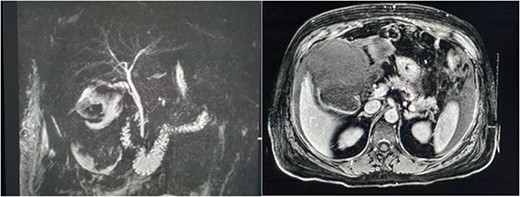

Magnetic resonance imaging (MRI) of the liver and magnetic resonance cholangiopancreatography (MRCP) were performed in the following days, which demonstrated a frank rupture of the gallbladder and a patent biliary tree (Fig. 3). After a few more days, the patient became peritonitic and a further CT was performed. This demonstrated a moderate volume of peritoneal free fluid and haematoma in the gallbladder fossa (Fig. 4). Ultrasound-guided drainage of peritoneal fluid was performed producing bilious fluid. ERCP was performed, which demonstrated ongoing leak from the gallbladder fossa (Fig. 5) and allowed placement of a covered biliary stent to divert flow away from the cystic duct.

CT demonstrating large volume of bilious peritoneal fluid with haematoma and calculus in the gallbladder fossa.